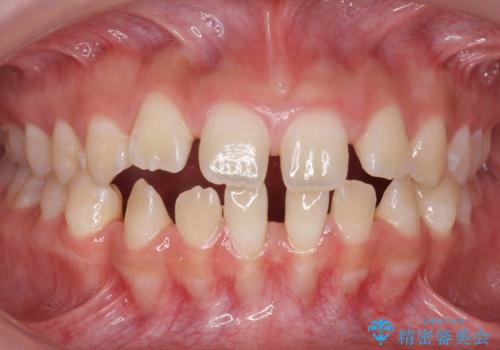

前歯のがたつきをなおしたい マウスピース矯正

担当医 大元洋佑

![[ マウスピース矯正 ] 前歯の角度・がたつきを治したい。の症例 治療前](https://seimitsushinbi.jp/wp/wp-content/uploads/2024/02/IMG_7820-500x350.jpg?v=1707810350)

![[ マウスピース矯正 ] 前歯の角度・がたつきを治したい。の症例 治療後](https://seimitsushinbi.jp/wp/wp-content/uploads/2024/02/8334681fa61954fc45ff8cef14f33166-500x350.jpg?v=1707810480)